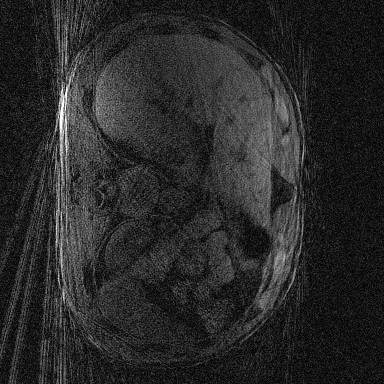

Supervised Deep-Learning (DL)-based reconstruction algorithms have shown state-of-the-art results for highly-undersampled dynamic Magnetic Resonance Imaging (MRI) reconstruction. However, the requirement of excessive high-quality ground-truth data hinders their applications due to the generalization problem. Recently, Implicit Neural Representation (INR) has appeared as a powerful DL-based tool for solving the inverse problem by characterizing the attributes of a signal as a continuous function of corresponding coordinates in an unsupervised manner. In this work, we proposed an INR-based method to improve dynamic MRI reconstruction from highly undersampled k-space data, which only takes spatiotemporal coordinates as inputs. Specifically, the proposed INR represents the dynamic MRI images as an implicit function and encodes them into neural networks. The weights of the network are learned from sparsely-acquired (k, t)-space data itself only, without external training datasets or prior images. Benefiting from the strong implicit continuity regularization of INR together with explicit regularization for low-rankness and sparsity, our proposed method outperforms the compared scan-specific methods at various acceleration factors. E.g., experiments on retrospective cardiac cine datasets show an improvement of 5.5 ~ 7.1 dB in PSNR for extremely high accelerations (up to 41.6-fold). The high-quality and inner continuity of the images provided by INR has great potential to further improve the spatiotemporal resolution of dynamic MRI, without the need of any training data.

翻译:在这项工作中,我们建议了一种基于IRI的方法,用这种方法来改进动态磁共振感应成像(MRI)重建,而该方法只是以高度低劣的 k-空间数据为基础,而该数据仅以磁共振坐标作为投入。具体地说,拟议的IRI将动态MRI图像作为一种隐含功能来表示,并将其编码到神经网络中。网络的权重仅从稀有的(k, t)空间数据本身中学习,而没有外部培训数据集或先前的图像。 利用基于IRI的强有力隐含性稳定化,同时不以清晰的动态和时空坐标坐标坐标坐标坐标作为投入。 拟议的IRIR将动态MRI图像作为一种隐含功能,将其编码到神经网络中。网络的权重仅从淡化的(k, t)空间数据本身学习,而没有外部培训数据集或先前的图像。